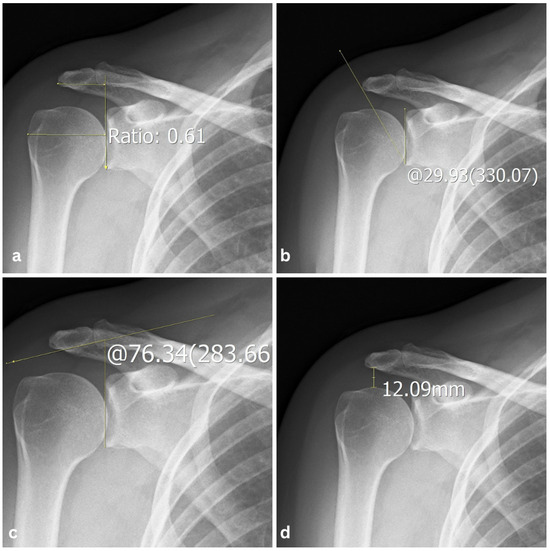

Association Between Osseous Shoulder Morphology and Pathoanatomical Characteristics of Calcific Deposits in Rotator Cuff Calcific Tendinitis

Background/Objectives: Rotator cuff calcific tendinitis (RCCT) is a common cause of shoulder pain. The role of acromial morphology in RCCT pathogenesis remains unclear. This study aimed to evaluate association between acromial morphological parameters and calcific deposit characteristics in patients with RCCT. Methods: We [...] Read more.